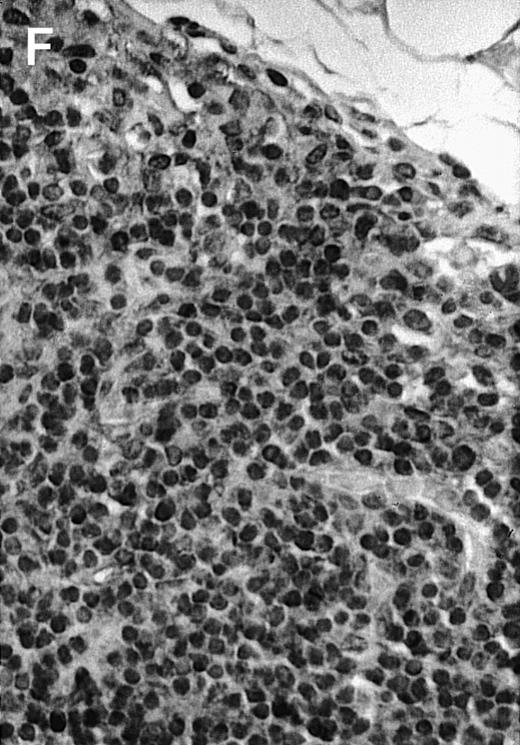

To explore the mechanisms of the protection from BCL growth, histologic analysis was performed on tumor tissue from mice treated with ST40L, ST, or PBS alone. In the mice treated with PBS alone, no cellular infiltrate expressing FasL was observed in the surrounding tissues and inside the BCL region (Figure 4A and D). In contrast, infiltrating lymphocytes expressing FasL were observed around the vessels and also scattered in the smaller tumor tissues in the mice treated with ST (Figure 4B and E). Small hard nodules (2-5 mm in diameter) were observed at the SC injection sites of the long-term survival mice that had been treated with ST40L. On histologic analysis, these small nodules were confirmed to be the result of an accumulation of lymphocytes, and not BCL cells (Figure 4C). These lymphocytes were also found to be strongly positive for FasL expression (Figure 4F). On the other hand, lymphocytes infiltrating in the nodules were stained by either CD4+ Ab or CD8+ Ab, but the ratio of CD4+ and CD8+ cells was not 1-sided (data not shown).

Histologic analysis of A20 tumors excised 21 days postchallenge from BALB/c mice immunized with ST40L.

(A) HE stain of a BCL region in a mouse treated with PBS alone. (B) HE stain of a smaller BCL region in a mouse treated with ST. (C) HE stain of a small hard nodule at the SC injection site in a mouse treated with ST40L. (D) Fas ligand staining of a BCL region in a mouse treated with PBS alone. (E) Fas ligand staining of a BCL region in a mouse treated with ST. (F) Fas ligand staining of a small hard nodule at the SC injection site in a mouse treated with ST40L. Original magnifications are ×400.